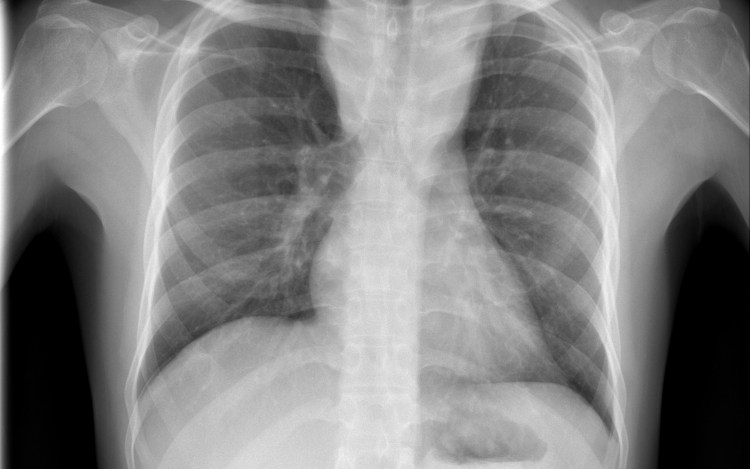

Terjed a tbc Szatymazon?

Hétfő reggel óta tbc-tesztet végeznek el a gyerekeken egy szatymazi általános iskolában, ahol egy hete fertőző tüdőbetegségben halt meg egy korábban ott dolgozó nő - közölték az M1 aktuális csatorna déli Híradójában.

A Délmagyar hírportál hétfő reggel írt arról, hogy februárig dolgozott a szatymazi iskolában közmunkásként az nő, aki tuberkulózisban (tbc) halt meg egy hete. Az ügyben rendkívüli szülői értekezletet tartottak. Az általános iskola 260 tanulója közül szülői beleegyezéssel 250-en végzik el a tbc-tesztet.

Az M1 tudósítója a helyszínről azt mondta: több szülővel beszéltek, ők nem voltak megriadva; elmondták, hogy az iskola azonnal tájékoztatta őket arról, mi történt a nővel, aki takarítóként dolgozott az iskolában február végéig. A tudósító megjegyezte, a tbc tüneteinek lappangási ideje 28-30 nap, ez az idő már letelt, de egyetlen gyereken sem tapasztaltak egyetlen tünetet sem.

Felidézték, hogy Magyarországon 1954 óta kötelező a tbc elleni védőoltás. Most az iskola diákjain biztonsági intézkedésként végzik el az úgynevezett Mantoux-tesztet, amely kimutatja, hogy védettek-e a tbc ellen. Ezt a tesztet később, három és hat nap múlva is megismétlik - hangzott el a Híradóban.

Április elején egy debreceni óvodában volt szükség hasonló intézkedésekre, mert az intézmény egyik dolgozója tüdőtuberkulózissal fertőződött meg.